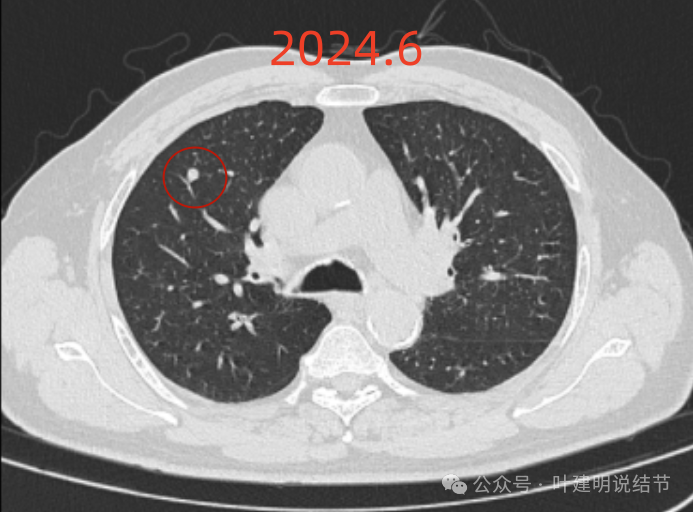

再看2024年6月时的影像:

右上没有明显变化,仍考虑良性可能性大。

左下也考虑良性,与2022年无明显变化。